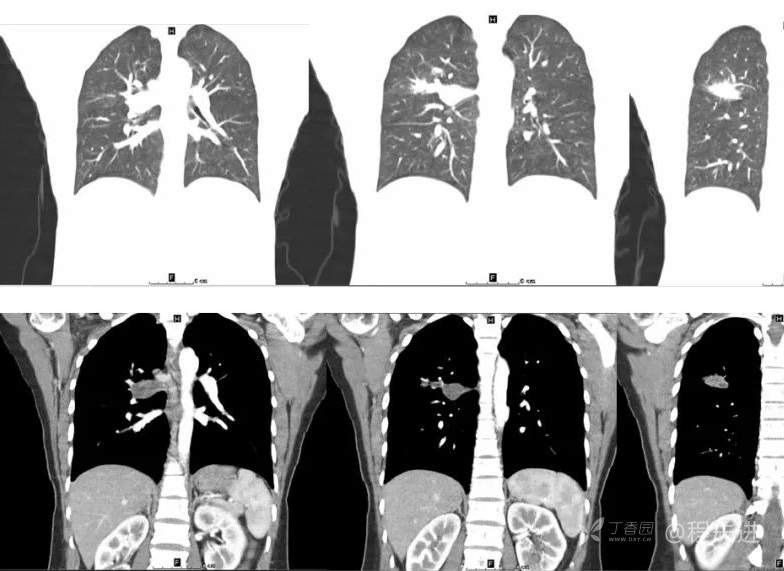

抗结核治疗后,复查

1年后术前复查